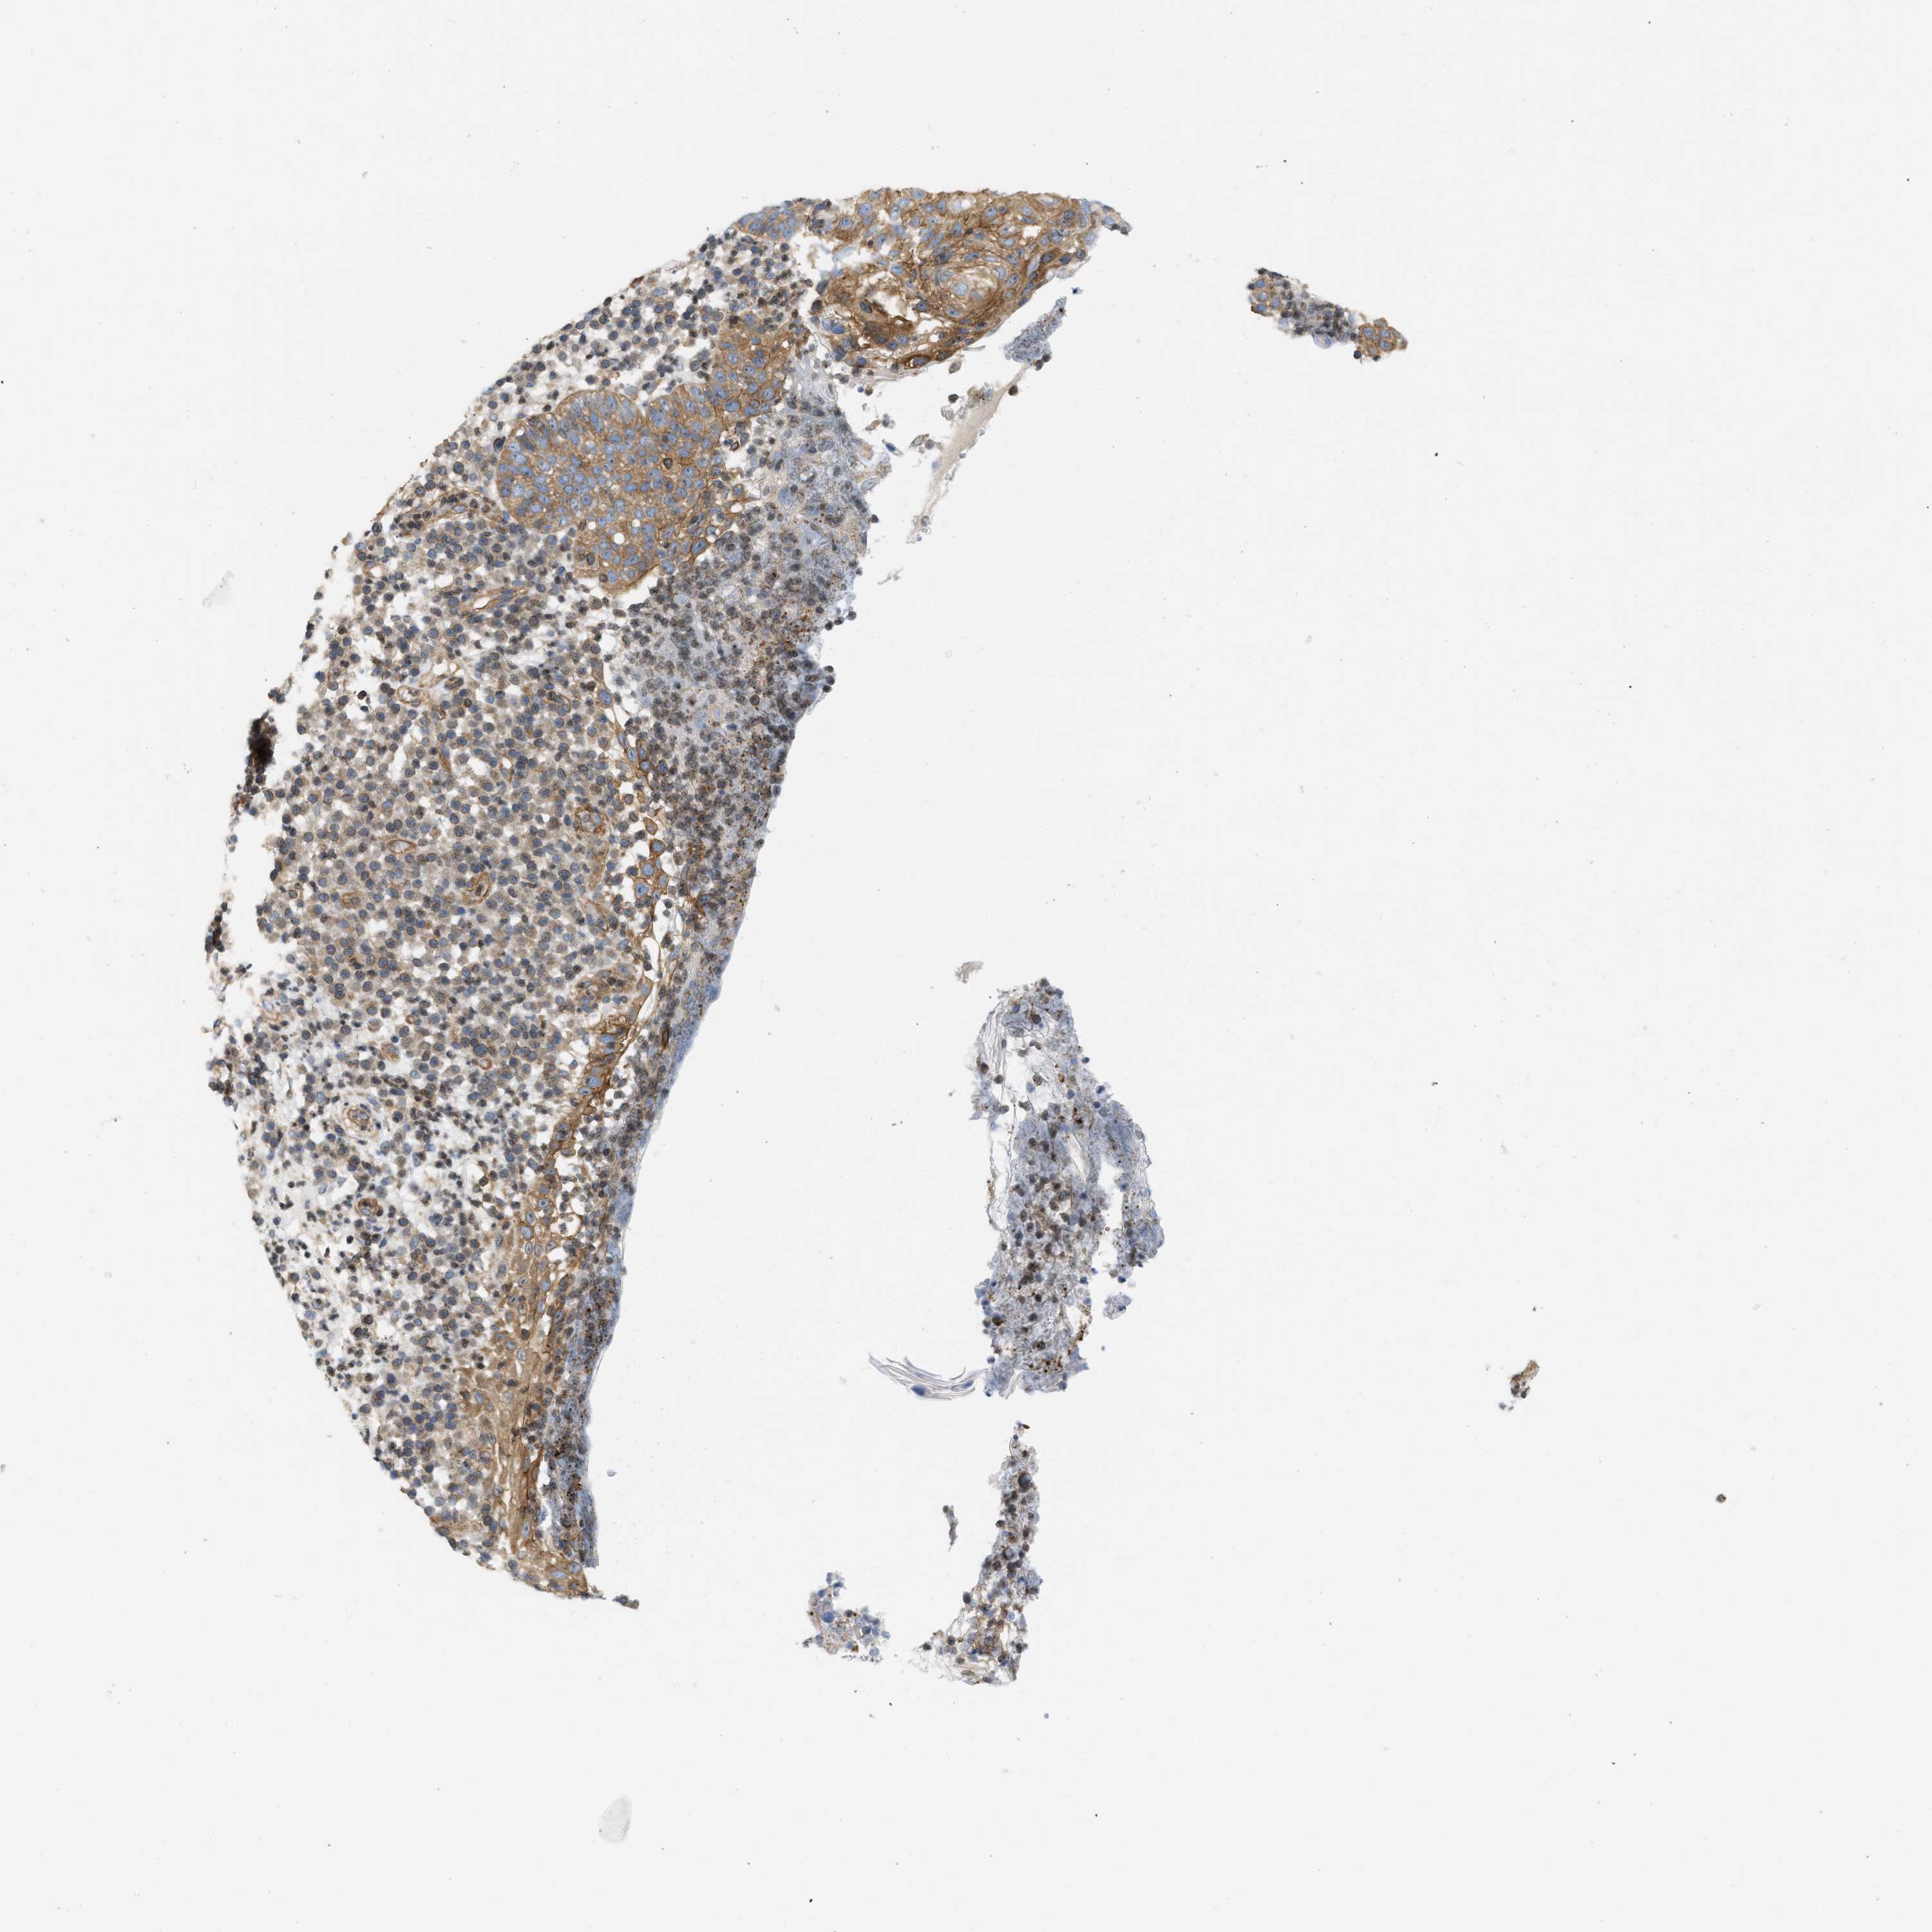

CANCER SKIN CANCER Show tissue menu

SKIN CANCER - Protein expressioni

A mouse-over function shows sample information and annotation data. Click on an image to view it in a full screen mode. Samples can be filtered based on level of antibody staining by selecting one or several of the following categories: high, medium, low and not detected. The assay and annotation is described here.

Each image is clickable and will lead to virtual microscopy that enables deeper exploration of all samples and also displays staining intensity scores, fraction scores and subcellular localization as well as patient and tissue information for each sample.

Antibody HPA017286

Staining

High

Medium

Low

Not detected

Intensity

Strong

Moderate

Weak

Negative

Quantity

>75%

75%-25%

<25%

None

Location

Nuclear

Cytoplasmic/membranous

Cytoplasmic/membranous,nuclear

Squamous cell carcinoma in situ, NOS

Squamous cell carcinoma, NOS

Squamous cell carcinoma, metastatic, NOS

Basal cell carcinoma

Adnexal tumor, benign